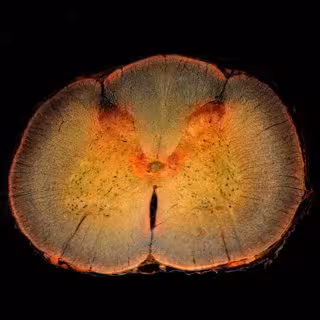

Sección transversal de la médula espinal, incluido el cuerno dorsal de la médula espinal, donde se procesa el dolor.

Sección transversal de la médula espinal, incluido el cuerno dorsal de la médula espinal, donde se procesa el dolor. - DW_ROSS / FLICKR - Archivo